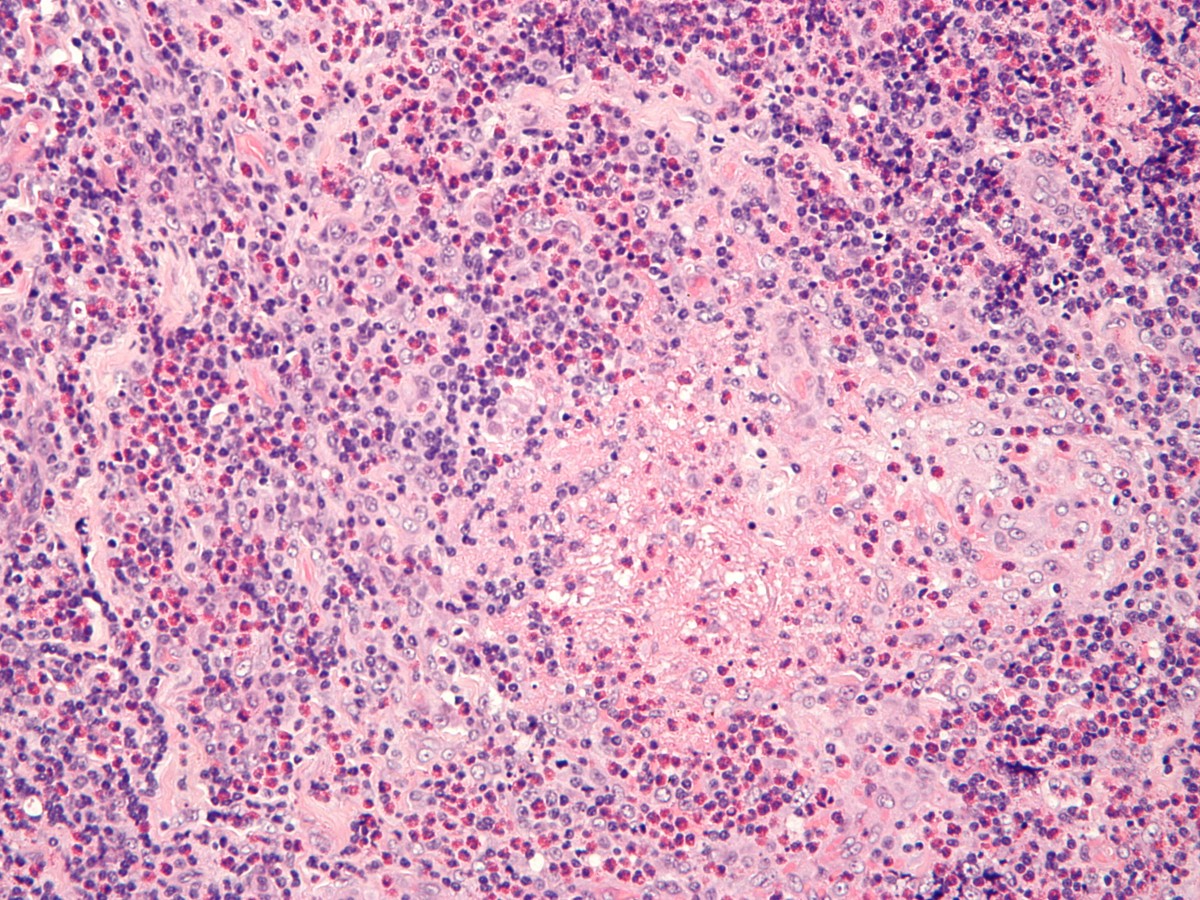

Histologie:Histologisch ziet men verspreid over het

hele preparaat lymfoïde infiltraten met een kiemcentrum, en veel eosinofielen.

Tevens een proliferatie van endotheelweefsel met dikwandige vaten en hobnail

endotheelcellen (zie ook onder

hobnail

hemangioom). Het infiltraat is polymorf en niet klonaal.

![Kimura's disease (click on photo to enlarge) [source: Michael Bonert (Nephron) - Wikimedia - Creative Commons License 3.0] Kimura's disease](../../../images/kimura-disease-2z.jpg) |

![Kimura's disease (click on photo to enlarge) [source: Michael Bonert (Nephron) - Wikimedia - Creative Commons License 3.0] Kimura's disease](../../../images/kimura-disease-3z.jpg) |

| Kimura's

disease (PA) |

Kimura's

PA foto's: Michael Bonert (Nephron) - Wikimedia (Creative Commons License

3.0)